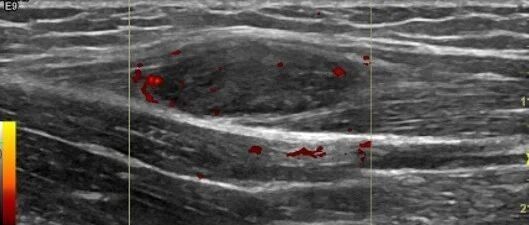

左前臂肿物,呈低回声,你考虑什么? 丁香园超声时间 · 公众号 · 医学 · 1 年前 · |